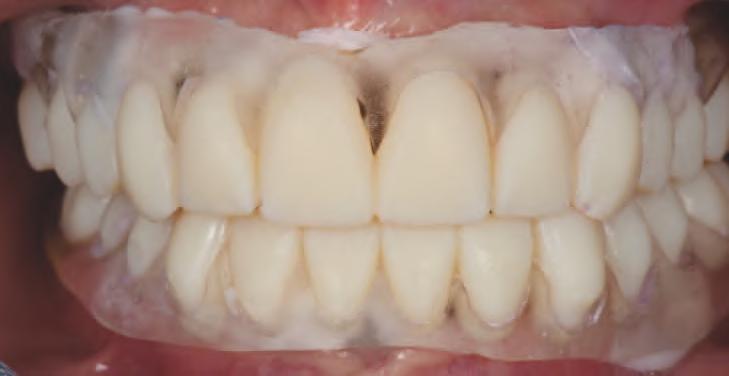

15. Vedere extraorală a restaurărilor finale livrate.

16. Vedere intraorală a restaurărilor finale mandibulare livrate.

În cab net, restaurăr le prov zor au fost deșurubate ș îndepărtate d n cav tatea orală pentru ca restaurăr le f nale să poată f l vrate ș strânse cu un cuplu de 15 Ncm, conform recomandăr producătorulu (f g. 15,16). Ajustăr le ocluzale f nale au fost m n me ș efectuate ntraoral pr ntr-o ultmă lustru re a zonelor ajustate.

CONCLUZII

Actualmente nstrumentele d gtale în stomatolog e perm t furnzor lor să obț nă rezultate prev zb le în mod ef c ent pentru cazur complexe precum reab l tăr le full-mouth. Ex stă benef c cons derab le în ut l zarea fotograf e d g tale 2D sau a scanăr lor fac ale 3D pentru a crea pac enț v rtual . Acest lucru perm te cl n c en lor ș tehn c en lor să exam neze reperele estet ce ș funcț onale pe măsură ce cazul este procesat, de la d agnost c până la fabr carea restaurăr lor f nale.